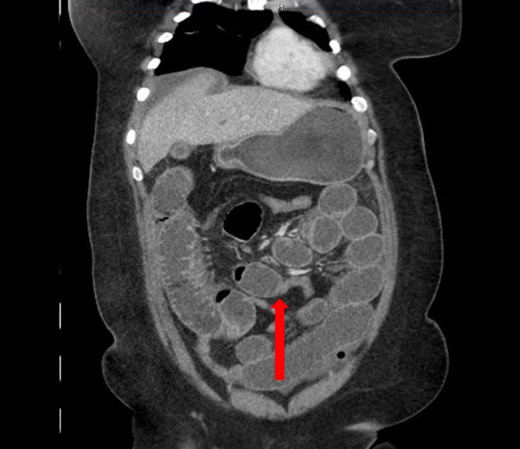

A 40-year-old woman presented to the emergency department with abdominal pain for 4 days. She had previously been seen at an outside hospital 3 days earlier, and was diagnosed with biliary colic. Her pain was constant, and was associated with nausea and vomiting. She had a history of a cesarean section, but no other abdominal surgeries. Her vitals were within normal limits: afebrile at 36.9°C, heart rate 71 beats/minute, blood pressure 143/62 mmHg, respiratory rate 18 breaths/minute, and oxygen saturation 97% on room air. On abdominal exam, she was distended, tender, demonstrated voluntary guarding and was positive for peritonitis. Laboratory values were significant for a white blood cell count of 16.1 K/ul, with 80.2% neutrophils, hemoglobin 14.9 g/dl, hematocrit 45.4%, platelets 349 K/ul and lactic acid 0.9 mEq/L; her chemistry was unremarkable. A computed-tomography (CT) scan of the abdomen and pelvis that was obtained prior to surgical consultation demonstrated the proximal two-thirds of small bowel dilated up to 4 cm, with a sharp transition point in the left mid-abdomen, and collapsed small bowel loops near the cecum. The colon was mostly collapsed. A few distended loops bulged into a paraumbilical hernia, which was 6 cm wide and not the cause of obstruction (Figs 1–3).

Coronal view: arrow pointing to the sharp transition point, where the distal end of the closed loop small bowel herniated through a hole in the sigmoid epiploica, demonstrating collapsed small bowel distally.